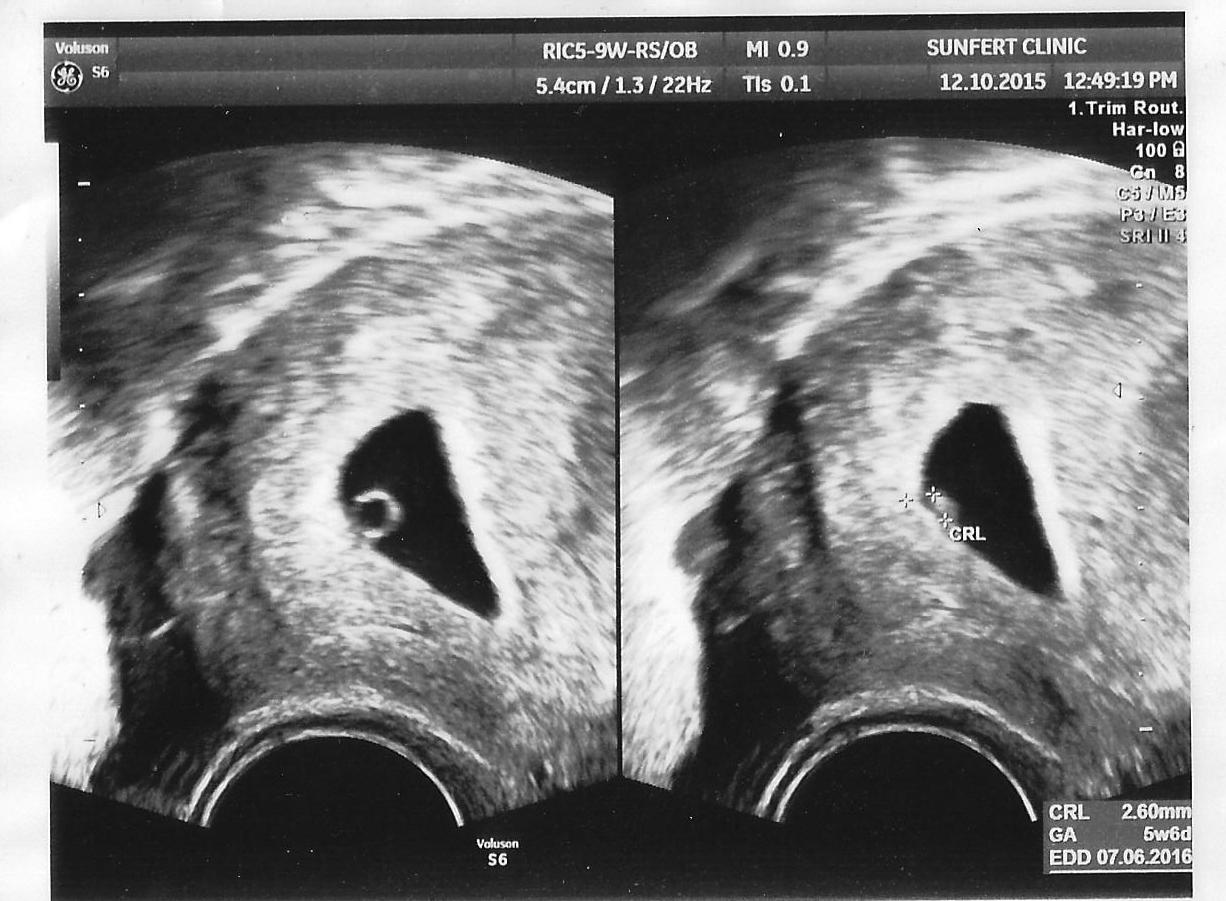

5 weeks ultrasound

This is the first time I set my eyes upon Lil’ BB. BB was just a little round ball. And we could actually see BB’s heart fluttering away. Only 5 weeks old. Awww… 5 weeks, 2.6 mm in size and the heart is already beating. Amazing. Can’t help to feel that Lil’ BB is so small and so fragile.